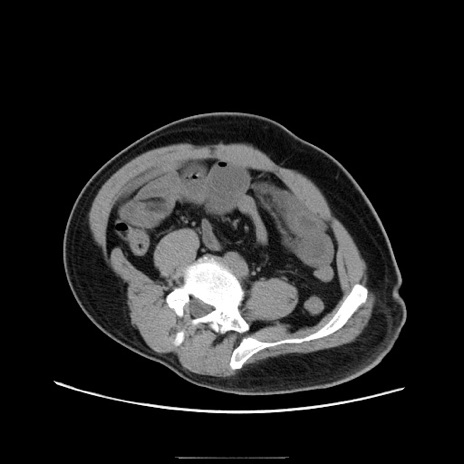

冠状断像

【症例】50歳代男性

【主訴】腹痛

【現病歴】AVMからの被殻出血のため回復期リハ病棟入院中。 本日午後3時頃急に下腹部痛が出現した。

【既往歴】AVM、被殻出血、虫垂炎、高血圧

【身体所見】意識晴明、左半身不全麻痺、会話の理解は良好、36.5°C、腹部:膨隆、全体に板状硬、下腹部正中に圧痛点あり、反跳痛-、筋性防御不明、右下腹部にope scar

【データ】WBC 9400、CRP 0.06